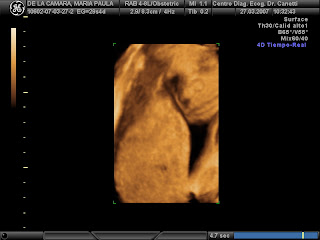

Presentando a Abril...

A ver, mirá para la cámara, Abril...

Así es... ah, bueno, también bosteza... ¿le aburrieron las fotos?